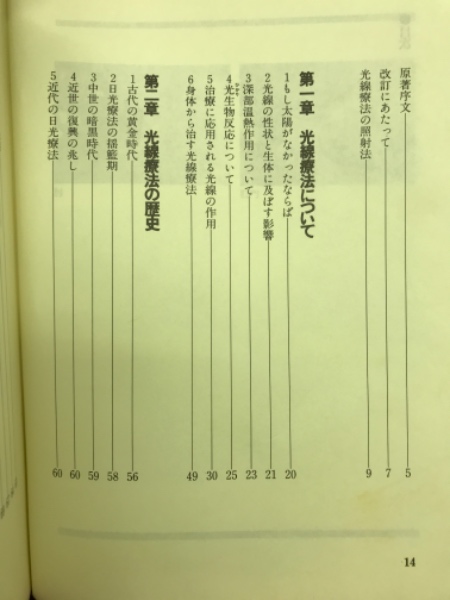

71B-RQqTOVS.jpg。光線療法学 (改訂増補版) | 原著者 宇都宮義真 改訂者 宇都宮。光線療法学(宇都宮義眞著) / 古本倶楽部株式会社 / 古本、中古本。宮崎県産 都城ブランド米 ひのひかり 5㎏×2袋。 閉じる